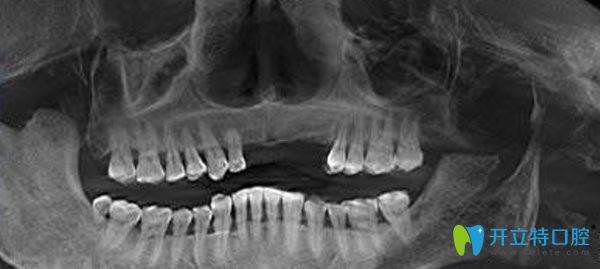

佳士潔口腔種植牙3D檢查圖片:

劉媽的種植牙過(guò)程就這樣開始啦!來(lái)院后做完口腔檢查,劉媽一直擔(dān)心缺牙數(shù)量多能不能種牙?接診的是李永平院長(zhǎng),經(jīng)過(guò)口腔檢查是多顆牙缺失,為她推薦了“德國(guó)種植牙技術(shù)”,固位性好、咀嚼功能強(qiáng)大,美觀舒適、酷似真牙,適用于全口/半口牙缺失的顧客。只需微小切口,精準(zhǔn)植入牙骨,降低創(chuàng)傷程度,手術(shù)安全副作用小。